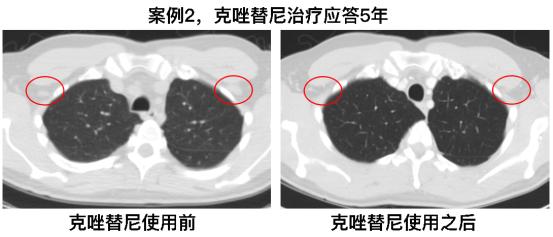

案例二

第二个案例是一名47岁从未吸烟的男性,病理诊断为肺腺癌。FISH检测发现ALK阳性的癌细胞比例也是非常高,达到了58%。患者每天两次服用克唑替尼,计量为250mg,对治疗产生了部分应答,下图红色标注的是对治疗应答的淋巴结,且维持了60多个月的时间(5年)。